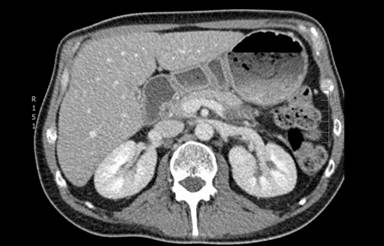

He was commenced on chemotherapy according to the UK acute lymphoblastic leukaemia protocol (UK ALL XII trial). Induction phase 1 consists of intravenous daunorubicin 60 mg/m2 and vincristine 1.4 mg/m2 at days 1, 8, 15 and 22. Also oral prednisolone 60 mg/m2 days 1-28, intramuscular asparaginase 5,000 IU/m2 at days 17, 19, 21, 23, 25, 27, 29 and intrathecal methotrexate 12.5 mg on day 24. Bone marrow reassessment is conducted on recovery of counts, at or after day 28 to establish remission status. Subsequent treatment involves a second induction phase, intensification with high dose methotrexate and if in study (patient not in trial), a randomisation to either transplantation or further chemotherapy. The latter involves cranio-spinal irradiation followed by 4 cycles of consolidation and then 1 year of maintenance chemotherapy. During this time he developed diabetes mellitus due to pancreatic dysfunction, possibly secondary to leukaemic infiltration or as a consequence of corticosteroids and chemotherapy. A significant drop in bilirubin, alkaline phosphatase and white cell count was noticed within a week, and after 25 days of treatment his jaundice completely resolved. Follow-up CT showed a reduction of the mass from 4 cm to 1.7 cm in the pancreatic head and from 4.5 cm to 1.6 cm in the body of the pancreas. The left para-aortic node decreased in size from 1.7 cm to 1.1 cm (Figure 3) and no new sites of disease were identified. After initial induction chemotherapy, a repeat bone marrow assessment showed complete remission with no residual disease by flow cytometry (Figure 4). However, because of the adverse cytogenetics, he has been referred for allogeneic bone marrow transplantation in first remission.

Figure3. CT scan showing resolution of the pancreatic mass after chemotherapy. |